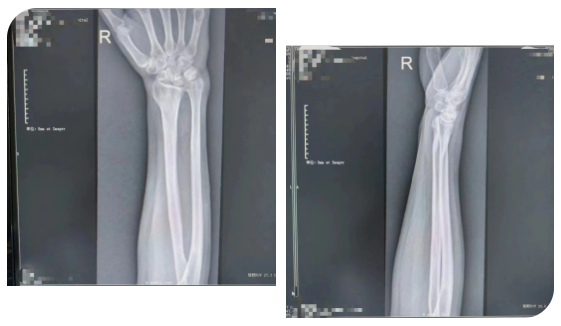

马女士(化名)于2年前因外伤导致“右侧桡骨远端骨折”,找当地赤脚医生行“包草药”治疗。后逐渐发现右侧腕部尺侧凸起畸形,腕关节尺偏活动受限,患者未予重视。

近3月来,患者抱孙子后出现右尺侧腕关节疼痛,前臂旋前时疼痛加重,握力减弱明显,感受到身体的异样后,便到医院创伤外科就诊。

患者于门诊善相关检查后诊断为:右侧尺骨撞击综合征。创伤外科主任医师王磊及其团队在仔细评估后,经过周密的术前准备,在臂丛麻醉下行“右侧尺骨短缩截骨”。该术式通过恢复中立或负向的尺骨变异来解压尺腕关节从而缓解尺骨撞击症状。